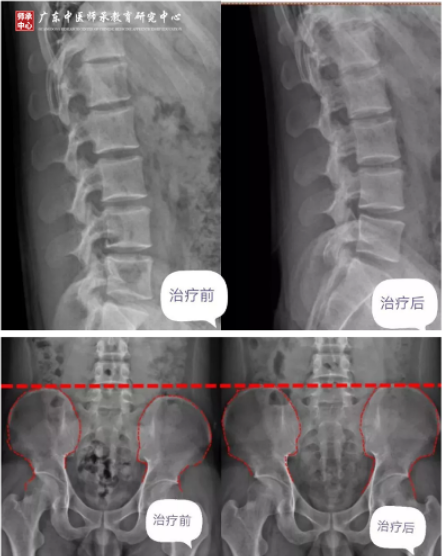

吴先生,25岁,做批发,经常弯腰搬货物,站立坐腰痛,一侧腿麻,开车时疼痛难忍,病因在于腰椎生理曲度变直,骨盆高低错位。

2019年8月21日——2019年10月30日,通过骨筋脉三联疗法治疗,如今已能自己开车。

三联疗法治疗前后对比